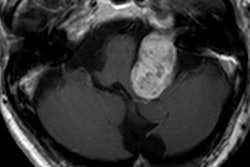

Video from ECR 2018: Thomas Beyer on hybrid imaging VIENNA – The successful clinical implementation of hybrid imaging in Europe still appears to be a long way off. Major challenges remain, particularly in terms of training and education and availability of equipment. Thomas Beyer, PhD, professor of physics of medical imaging, Medical University of Vienna, speaks about an extensive new survey that sheds light on the issues to be resolved. Caption: Prof. Thomas Beyer from Vienna Video produced by Christof. G. Pelz I GRAFIFANT Creation. Grafik. Photo I www.grafifant.atVideo from ECR 2018: Thomas Beyer on hybrid imaging